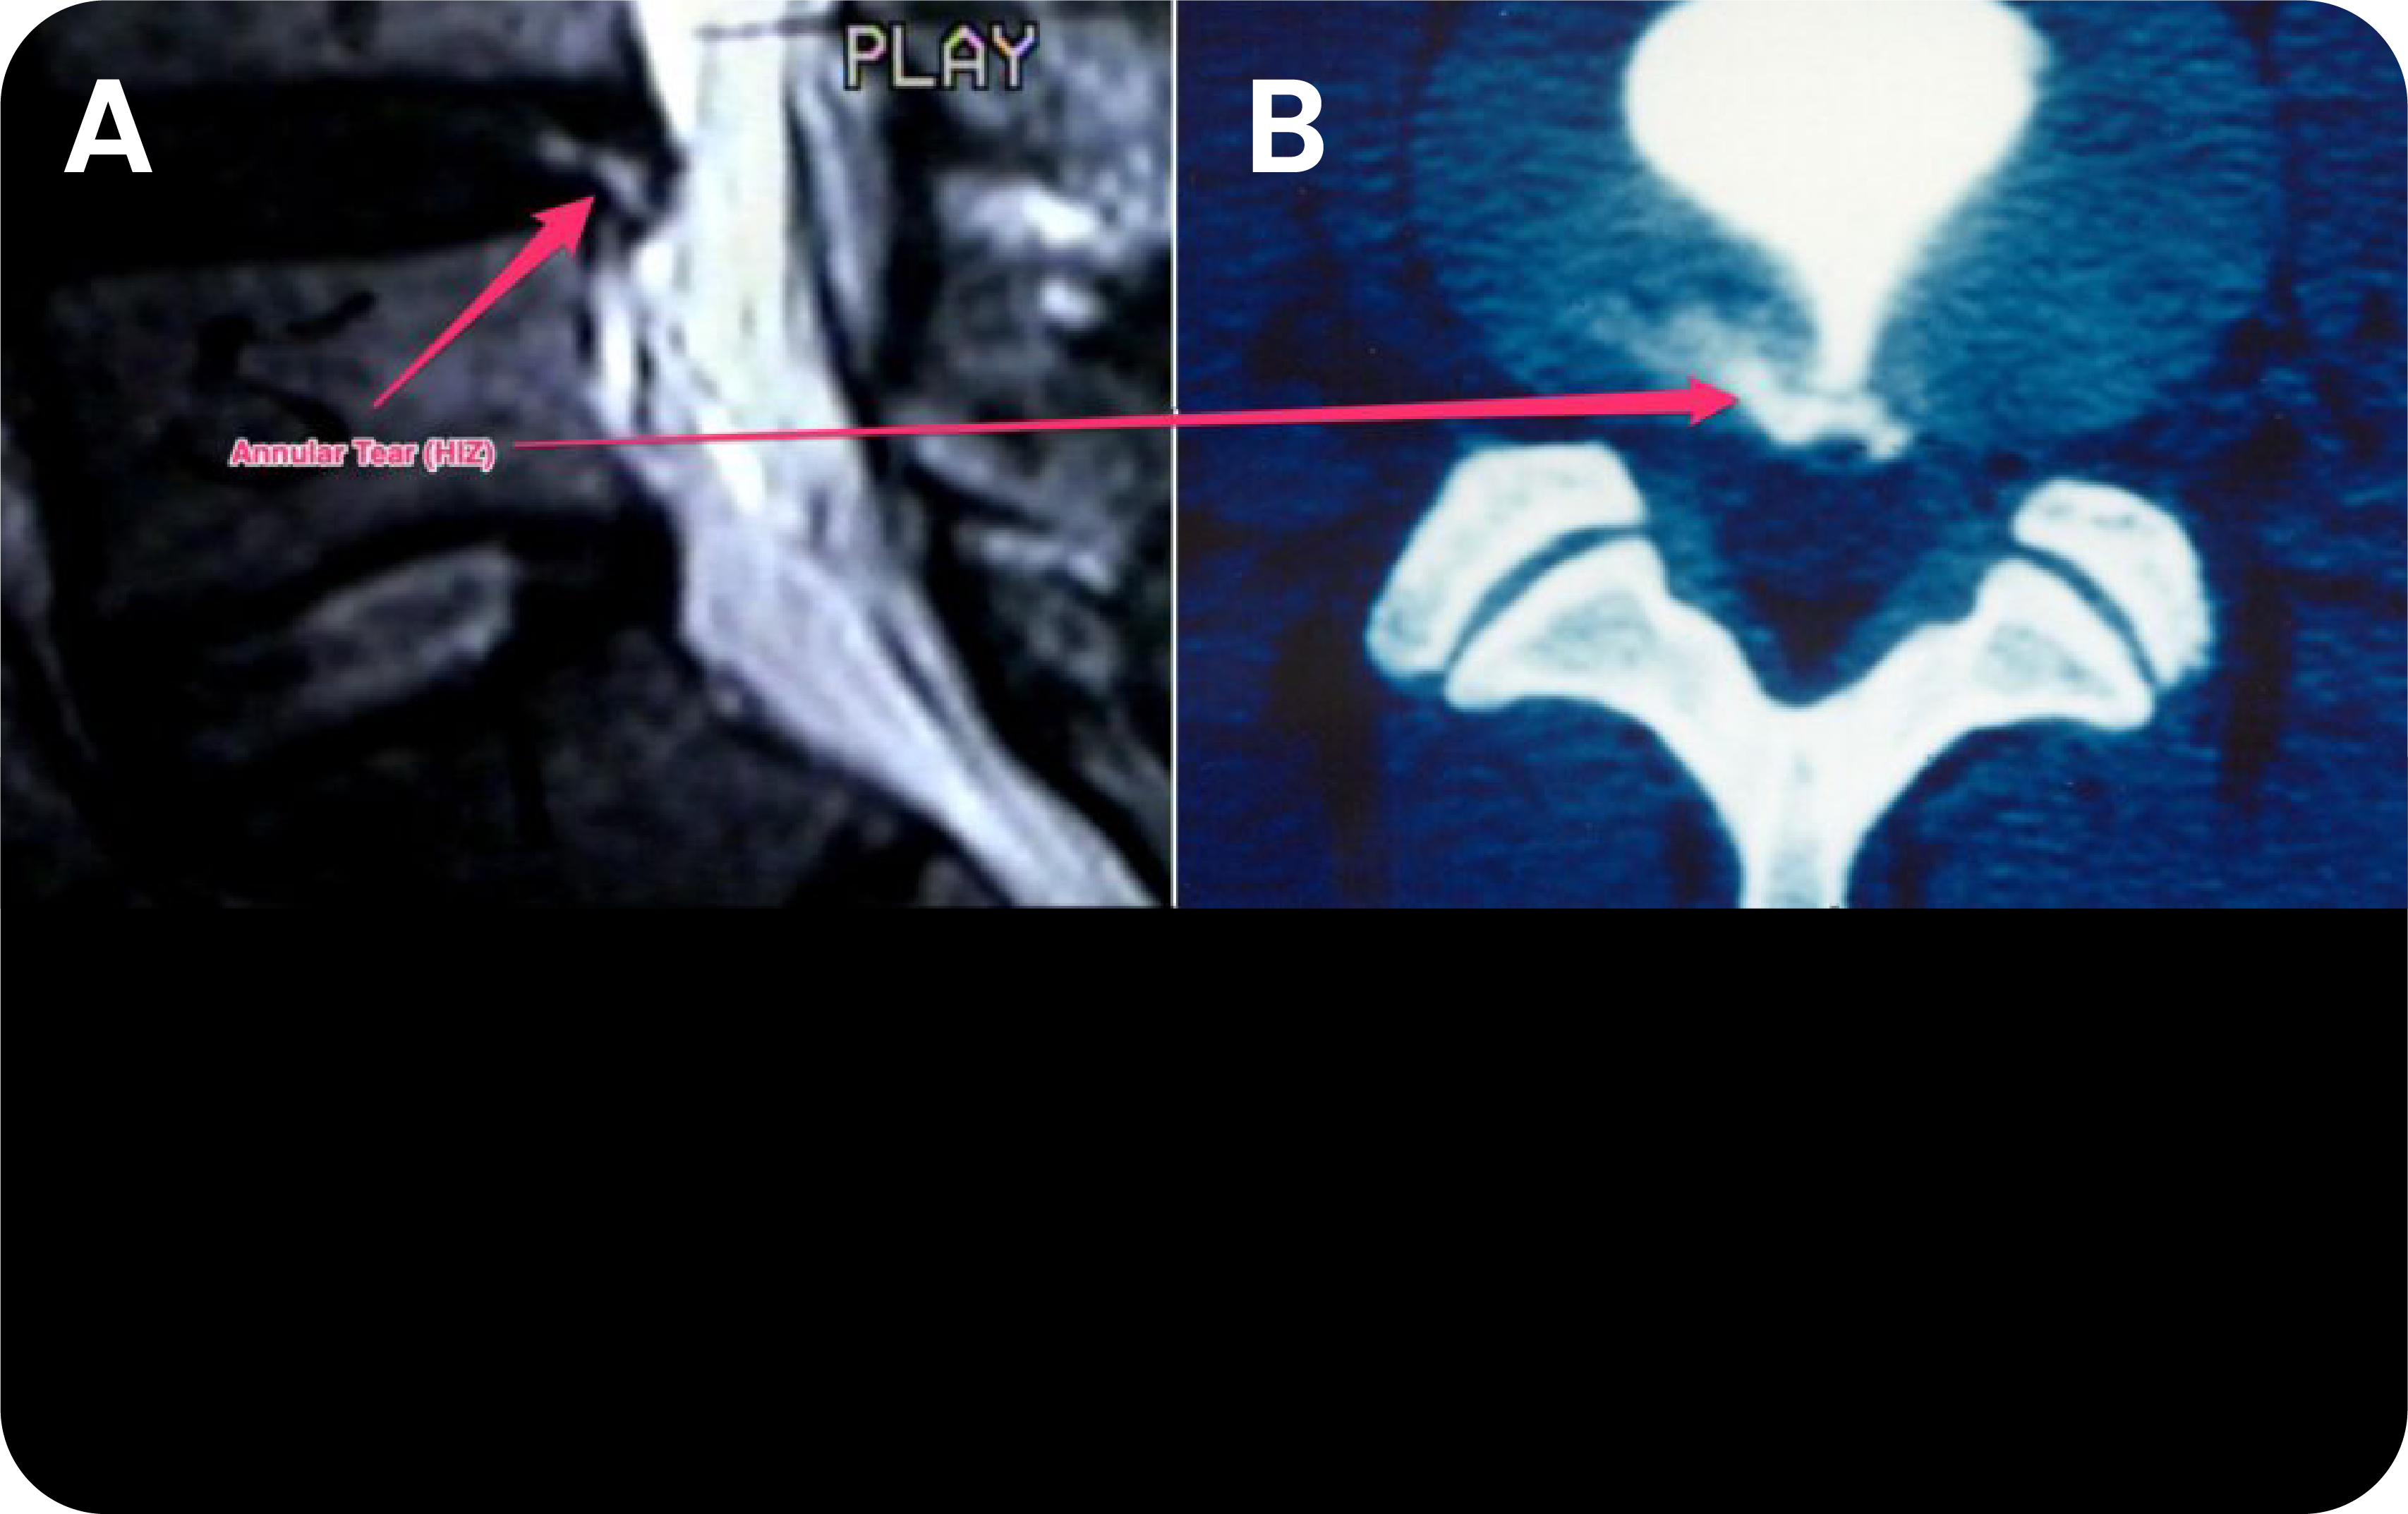

Inter-vertebral disc represents an essential part of the human spine. It consists of two parts: a.) The inner, gel-like core also known as nucleus pulposus; and b.) Outer lamelar parts also known as Annulus fibrosus. Substantial body of scientific evidence suggest that annular tear – structural alteration of the disc (Fig.1) whether due to the injury or aging is a root cause of low back pain and loss of spine function.

A. MRI image of the lumbar inter-vertebral disc showing high intensity zone (HIZ – Arrow) consistent with the damage to outer layer of the disc.

B. CT annulogram – The image shows leak of contrast agent out of confine of the disc confirming damage to the annulus fibrosus of the disc.